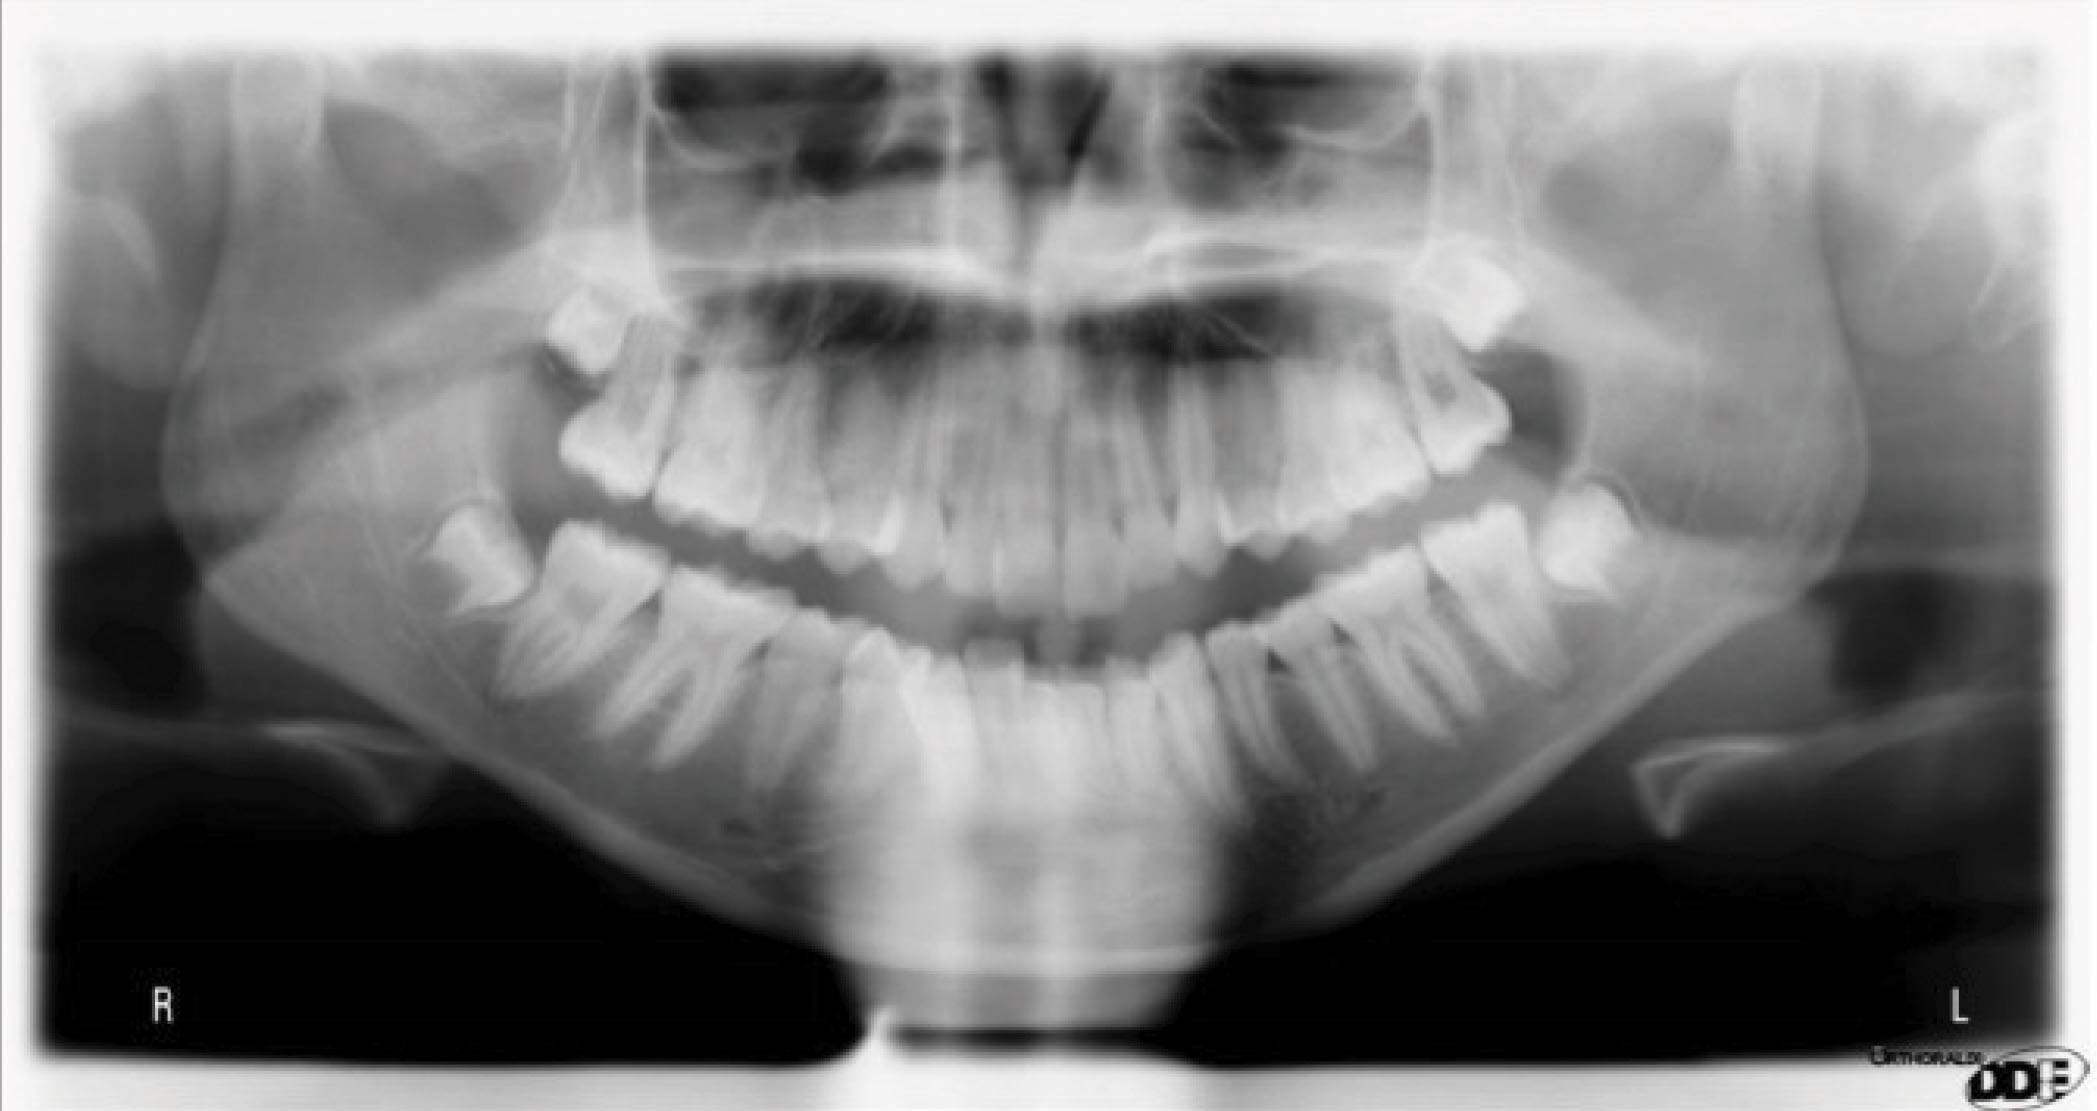

یک بیمار با اوربایت و اورجت طبیعی و کرادینگ شدید در دو قوس است. لترالهای بالا لبیالی شدند، کانین راست پایین تا حدی بلاک شده است و پروفایل طبیعی میباشد. بیمار کرادینگ شدید و قوس فکی تنگی دارد (شکلهای 29-6 الی 31-6). لترالهای بالا شدیداً پروترود هستند. برای کنترل این لترالها بعداً بیشتر صحبت میکنیم که اختلاف بین اکستروژن واقعی آن با اکستروژن نسبی آن را ببینیم.

آنالیز فضا: اکسپنشن پروترود نمودن استریپ کشیدن

آنالیز زیبایی: کریدور باکالی تنگ ساپورت لب مثلث تاریک

ثبات درمان افزایش عرض بین کانینی ثابت بماند اکسپنشن خلف 2-3m در هرطرف

شکل 29-6

شکل 30-6

شکل 31-6

برای اصلاح کرادینگ بیمار کارهای زیر را مدنظر داریم:

• اکسپنشن خلفی

• پروترود نمودن قدامیها

• استریپ

کوریدور باکالی تاریک به همراه تنگی ماگزیلا مشاهده میشود. اکسپنشن خلفی در حد 2-3mm در هر سمت برای اصلاح تنگی قوس برای رسیدن به یک لبخند زیباتر و پُرتر کمک میکند، ولی عرض بین کانینی بیمار باید حفظ بشود.

شکلهای 33-6 و 34-6 نتایج درمان را نشان میدهد. قوس فکی کاملاً مرتب شده است. عرض بین کانینی حفظ شده، اکستروژن نسبی لترال بالا را داریم و به نتایج زیبایی و فانکشنال خوبی رسیدیم.

با سوپرایمپوز کردن لترال سفالومتری در شکل 35-6 شاهد سه درجه پروترود شدن انسیزورهای پایین هستیم. ارتفاع عمودی ثابت ماند و کنترل خوبی در حفظ زاویه پلن مندیبل داشتهایم. رادیوگرافی OPG پایان کار (شکل 36-6) طبیعی است. مدت نگهدارنده ۳۰ ماه بود و همه چیز خوب حفظ شده است (شکل 37-6).